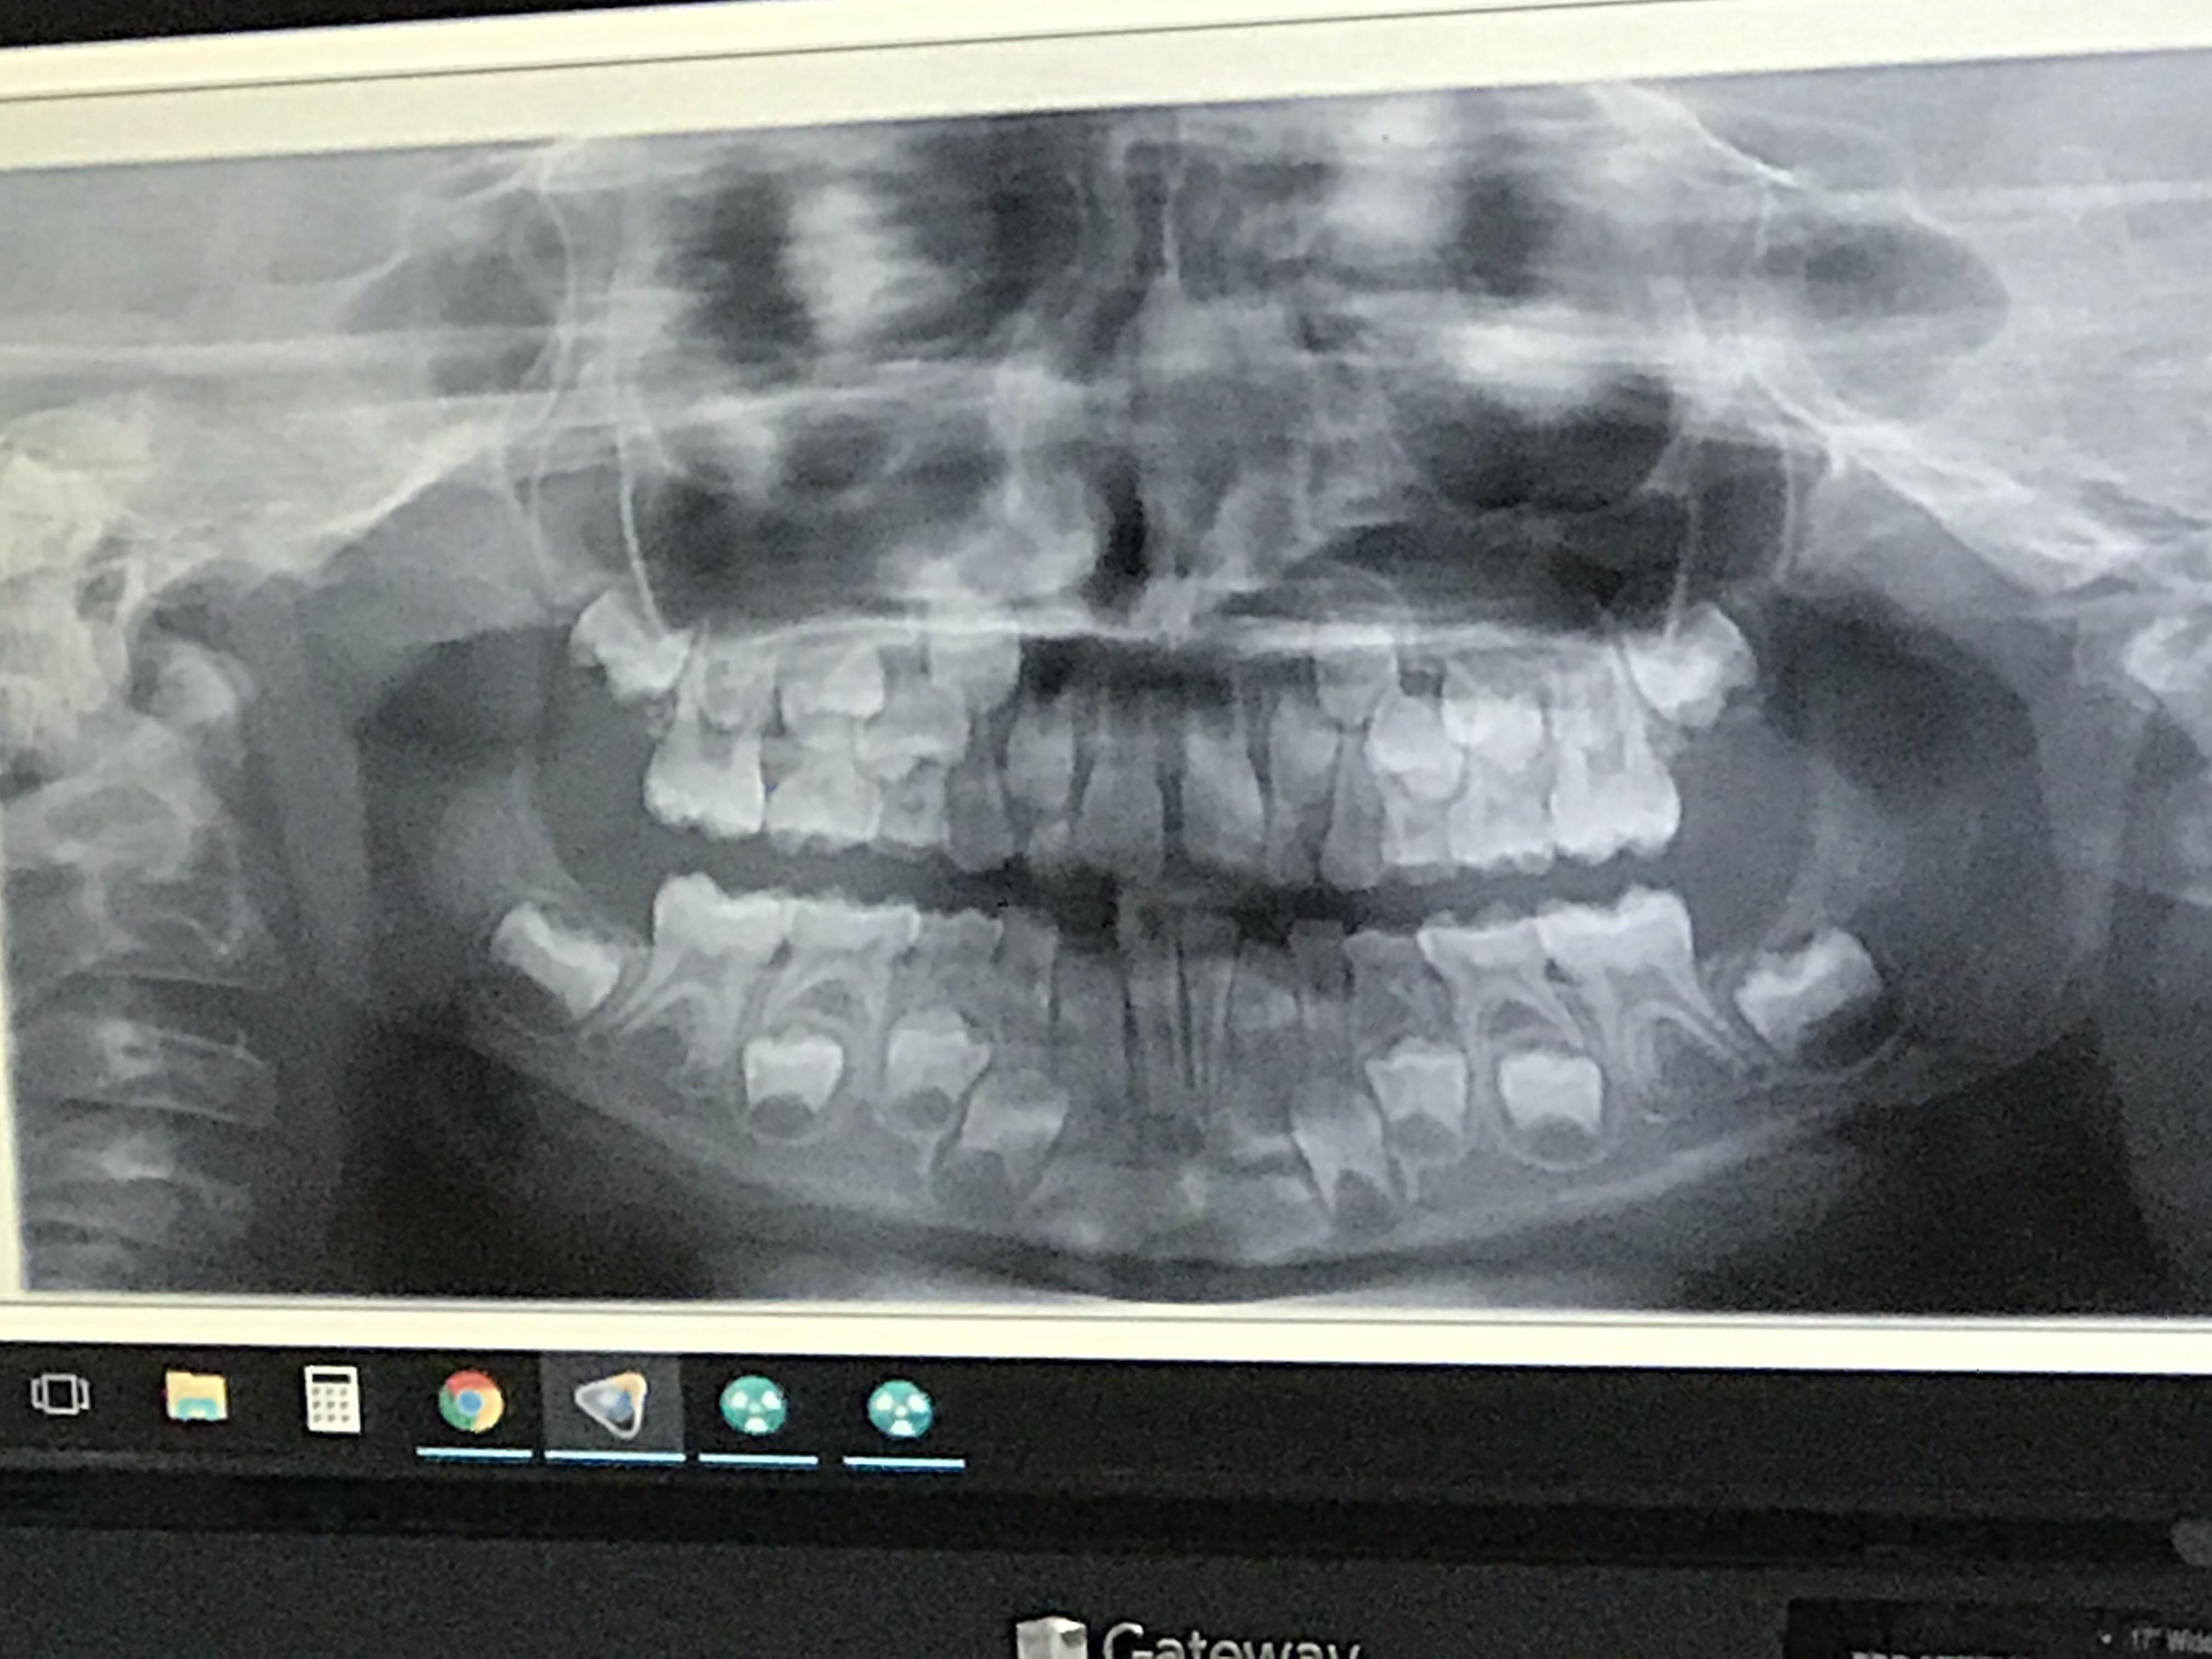

Infants were examined for clinical signs of rickets and had x rays of both wrists and forearms at 1, 3, 6, 9 and 12 months of age. No radiation remains in the body once the exam is complete. More it's the most common reason a child under 1 may end up at the hospital: The average child now gets seven scans that rely on radiation before age 18, one recent study shows.

Exposure to radiation at a very young age is a pretty solid concern for both medical professionals and parents. Infants were examined for clinical signs of rickets and had x rays of both wrists and forearms at 1, 3, 6, 9 and 12 months of age. But it is super safe for kids to be in. Use the lowest amount.

Infants were examined for clinical signs of rickets and had x rays of both wrists and forearms at 1, 3, 6, 9 and 12 months of age. Exposure to radiation at a very young age is a pretty solid concern for both medical professionals and parents. No radiation remains in the body once the exam is complete. Radiation is a.